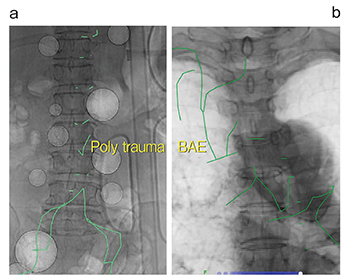

仮想透視画像は、多発外傷や気管支動脈塞栓術など1回の手技で多くの血管を選択する必要がある症例で、より有用性を発揮する(図3)。例えば1本の血管を探ることなくピンポイントで選択して3分短縮できたと仮定すれば、手技全体で10本の血管を選択すればトータル30分程度の時間短縮となる。

図3 多発外傷および気管支動脈塞栓術における仮想透視画像

a:多発外傷症例 b:気管支動脈塞栓術

多数の血管を選択する手技こそ各血管を速やかに選択できる意義は大きい。